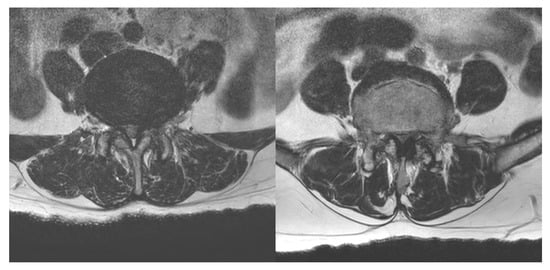

- Schizas, C.; Theumann, N.; Burn, A.; Tansey, R.; Wardlaw, D.; Smith, F.W.; Kulik, G. Qualitative grading of severity of lumbar spinal stenosis based on the morphology of the dural sac on magnetic resonance images. Spine 2010, 35, 1919–1924. [Google Scholar] [CrossRef]